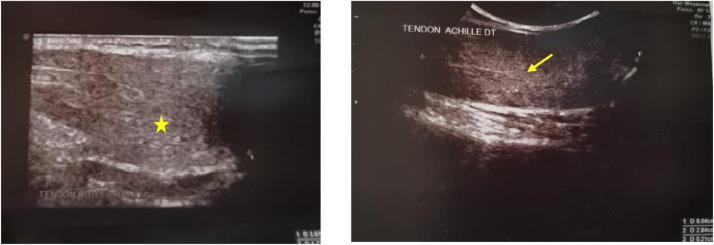

Cerebrotendinous xanthomatosis (CTX) is a rare hereditary disease characterized by a bile acid metabolic problem that causes cholesterol metabolites to accumulate in various organs. There are 2 types of CTX: traditional and spinal. The imaging characteristics are usual and allow for diagnosis confirmation. The brain's magnetic resonance imaging (MRI) reveals bilateral dentate nucleus lesions as well as modest white matter abnormalities. Tendon xanthomas (typically in the Achilles tendons on both sides) are a common finding. Cerebrotendinous xanthomatosis is a multidisciplinary diagnosis that must be made early to avoid neurologic injury and worsening. We show a CTX instance that has typical imaging and biology features.

脑腱性黄瘤病(CTX)是一种罕见的遗传性疾病,其特征是胆汁酸代谢问题导致胆固醇代谢产物在各个器官中蓄积。CTX有两种类型:传统型和脊髓型。其影像学特征较为常见,有助于确诊。脑部磁共振成像(MRI)显示双侧齿状核病变以及轻度白质异常。腱黄瘤(通常双侧跟腱处出现)是常见表现。脑腱性黄瘤病是一种多学科诊断疾病,必须尽早做出诊断以避免神经损伤和病情恶化。我们展示了一个具有典型影像学和生物学特征的CTX病例。